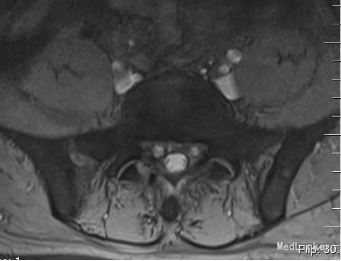

诊断:腰椎间盘突出症 (腰5/骶1髓核游离型) VAS评分:9分 ODI评分:96% 疼痛剧烈,右下肢难以伸直,坐卧不宁;给予常规脱水,激素,止痛等治疗无效;不同意手术,反复要求保守治疗。 保守治疗3天,患者疼痛仍无明显缓解,同意行手术治疗 手术方案:椎板间隙入路PELD 术后予以止痛,脱水,小剂量激素等治疗, 术后第二天:右下肢麻木疼痛明显缓解。查体:右小腿后侧及足背外侧皮肤触觉恢复;右足拇跖屈肌力4+级;右侧直腿抬高试验(-);右侧跟腱反射仍减弱。 术后第5天:出现右小腿及足底针刺样疼痛症状加重,麻木感,伴有右下肢间歇性抽搐,次数较频繁,以夜间为甚。查体:腰椎活动无明显受限,右小腿后面及右足背外侧触痛明显;双下肢屈伸肌力、肌张力基本正常;右侧直腿抬高试验(-),右侧跟腱反射仍减弱。 予以加大NSAID及地米治疗,效果不明显,夜间疼痛难以入睡。复查腰椎MRI,未见髓核再脱出,减压彻底 诊断:考虑右侧骶1神经根神经病理性疼痛 治疗: 普瑞巴林 75mg Bid;神经妥乐平 2# Bid; 阿米替林 25mg Bid 外加神经营养治疗 治疗1周后,症状明显缓解

术后10周:右侧臀部及右下肢烧灼样疼痛及皮肤触痛缓解,右下肢间歇性抽搐消失,偶感腰背部酸痛。查体:右足背外侧仍稍许麻木,无痛觉过敏,双下肢肌力正常,双直腿抬高试验(-).